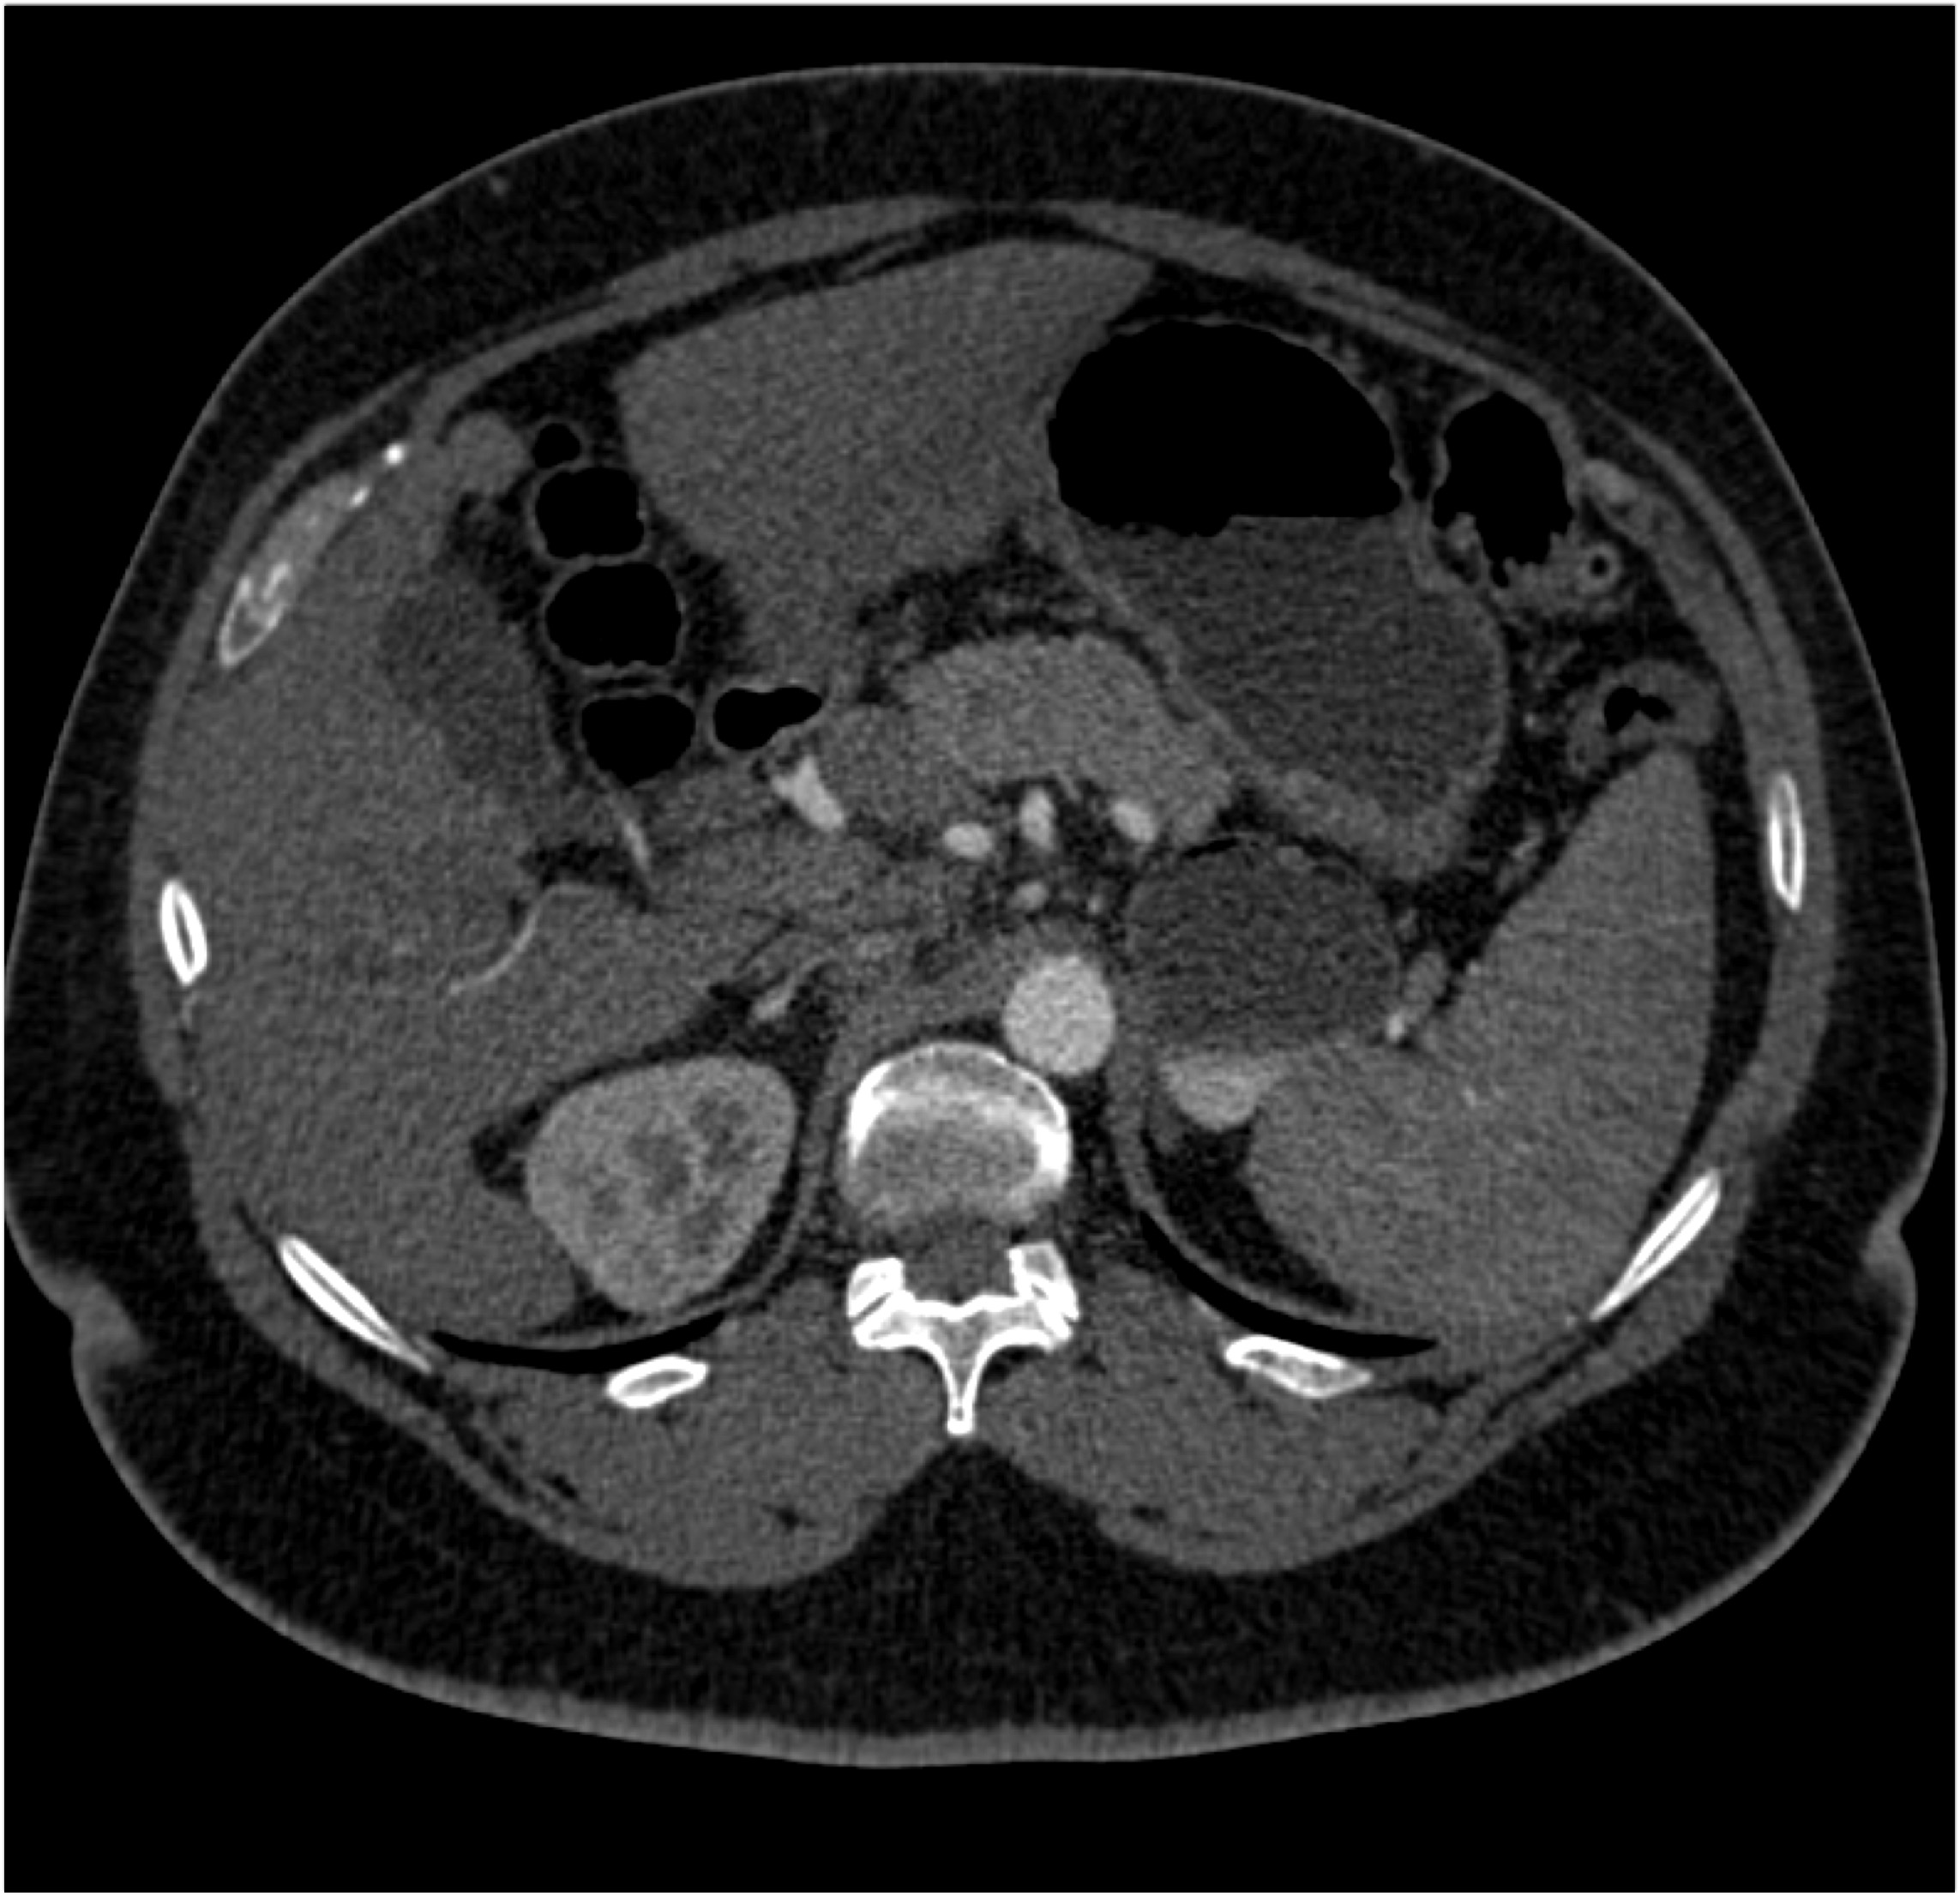

8) The most likely diagnosis in this case is?

clear cell renal cell carcinoma

large B-cell lymphoma

seminoma

renal abscess